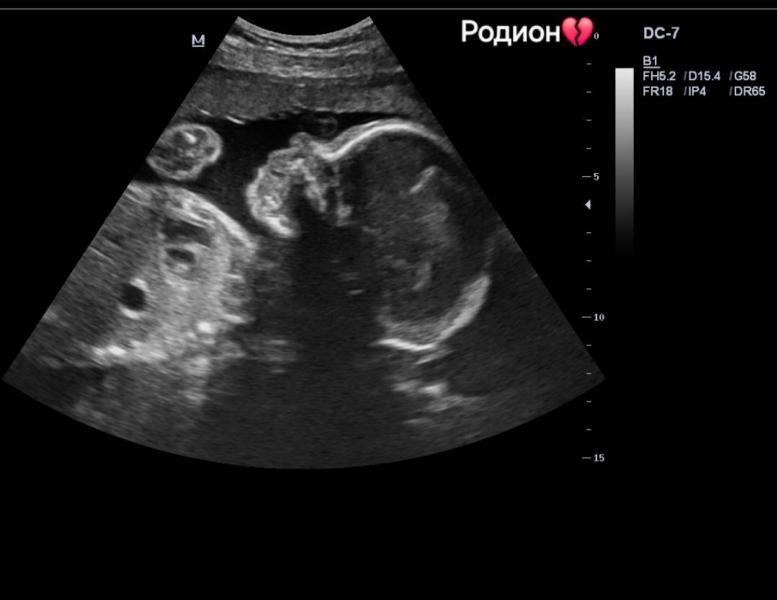

Ровно год назад я узнала, что сердце моего сына перестало биться... 💔

А через два дня будут роды, и 24 ноября родится мой сыночек — в День матери💔😭

Я так тебя люблю Родиончик